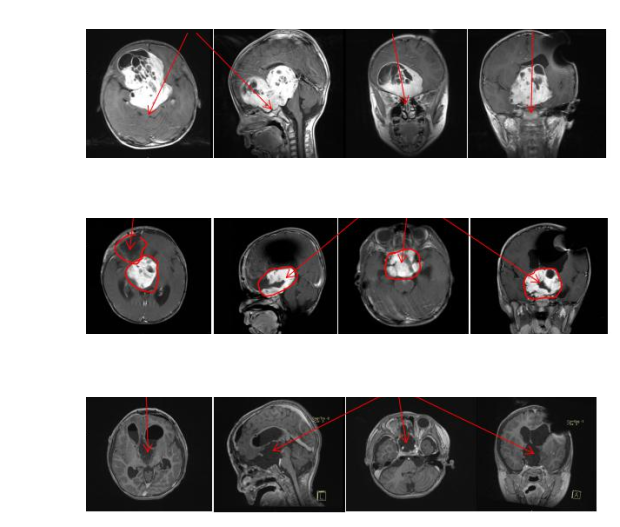

INC曾经与一名5岁儿童视路胶质瘤接触过,而这名年仅5岁的孩子因视神经胶质瘤病情严重,访问过国内神经外科医院后,各医院都表示这一位置无法手术,或者说手术风险很小。眼见孩子的病情一天天恶化,视力一天天模糊不清甚至几乎无光感,孩子父母决定带孩子通过INC国际神经外科医师集团,寻找国外更前沿的神经外科医师的治疗。较终,德国巴特朗菲教授在INC的手术下,切除肿瘤,视力逐渐恢复。

手术前和术后的磁共振图像对比显示。